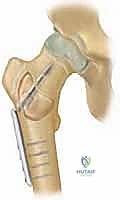

ثالثاً: العلاج الجراحي المتخصص (الكشط والتطعيم العظمي)

يُعد التدخل الجراحي هو المعيار الذهبي والعلاج الحاسم في الحالات التالية:

1. فشل العلاج بالحقن المتكرر.

2. الأكياس الكبيرة جداً التي تهدد بكسر محتم.

3. حدوث كسر مرضي بالفعل يحتاج إلى تثبيت.

4. معظم حالات كيس العظم المتمدد (ABC) نظراً لطبيعتها العدوانية واحتمالية الانتكاس العالية.

التخطيط الجراحي المسبق هو مفتاح النجاح. يقوم الدكتور هطيف بتحديد مكان الشق الجراحي وحجم النافذة العظمية المطلوبة للوصول إلى الكيس بأمان تام.

خطوة بخطوة: كيف يُجري الأستاذ الدكتور محمد هطيف جراحة الكشط والتطعيم العظمي؟

الجراحة في عيادة ومستشفيات الأستاذ الدكتور محمد هطيف في صنعاء ليست مجرد إجراء روتيني، بل هي عمل فني يجمع بين الدقة المتناهية واستخدام أحدث التقنيات الطبية